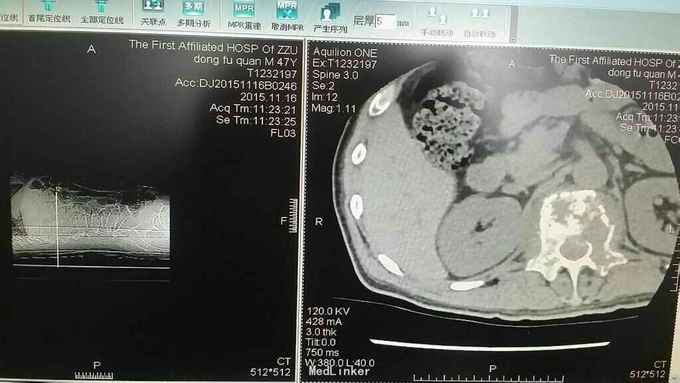

查体:脊柱生理曲度存在,无明显前凸,侧弯或后凸畸形,约胸10至腰5节段压痛及叩击痛阳性,双下肢肌张力正常,双侧股四头肌肌力约三级,双侧足背伸肌,踇背伸肌肌力约四级,双侧“4”字试验阴性,双侧直腿抬高试验阴性。肛周约15cm范围皮肤感觉减退。 辅助检查:肿瘤标志物无明显异常,血沉达120mm/h,血红蛋白111g/l,球蛋白与白蛋白比值倒置,血免疫球蛋白IgG达46.2g/l,明显升高。血清Kappa轻链与血清Lambda轻链比值明显升高。余辅助检查见下图。

通过影像学,实验室检查,骨髓穿刺检查及行CT引导下穿刺病理结果,患者多发性骨髓瘤诊断已明确。于全麻下行“腰1椎体病理性骨折病变清除减压内固定术”,术中可见病变压迫脊髓明显,彻底减压,术中出血较多,椎体破坏较重,未予骨水泥塑型,术后患者症状缓解明显,拆线后转至血液科进一步治疗。

多发性骨髓瘤是一种单克隆的浆细胞异常增生所致的恶性肿瘤,常以骨骼症状为首发,以脊柱最常累及,本例患者主要手术指征为持续且无法缓解的骨痛,并存在脊髓和神经根压迫症状,,主要影像学表现为穿凿样溶骨性改变,周围无硬化改变。很多全身骨现象无明显的阳性表现,增加了诊断的难度,上面提到的血沉升高,贫血,球白比倒置,血免疫球蛋白升高,骨髓穿刺综合判断,诊断明确后,一般行姑息性手术治疗,一般预后较差,随访见到生存期最长为4年。